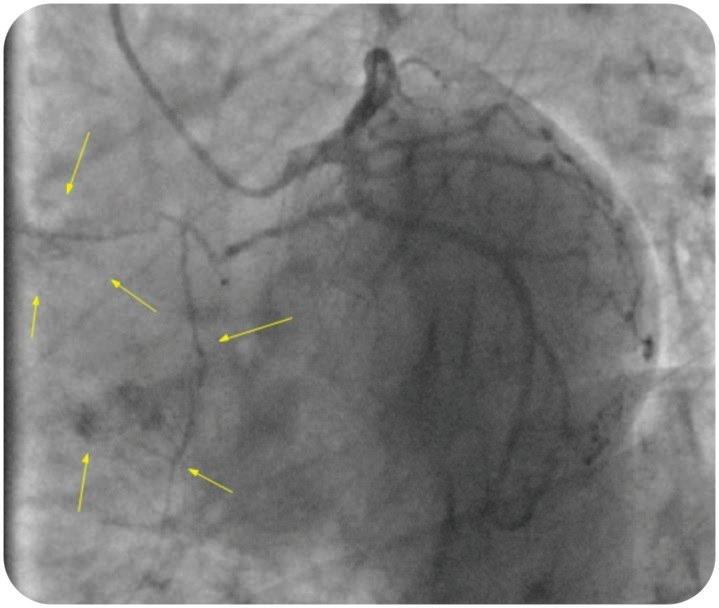

1. ИНВАЗИВНО ИЗСЛЕДВАНЕ ПО СПЕШНОСТ (<2 Ч.)

Пациентите с клинико-лабораторна констелация за СТЕМИ подлежат на инвазивно изследване в неотложен порядък. Кога е оптималният момент за провеждане на коронарна реваскуларизация при пациенти с остър коронарен синдром без СТ-сегмент елевация е обект на обстойни проучвания. В тях обаче, рядко се включват пациенти с хемодинамичен нестабилитет, животозастрашаващи камерни тахиаритмии, механични усложнения и декомпенсирали прояви на сърдечна недостатъчност. Тези пациенти подлежат на спешно инвазивно изследване, независимо от параклиничната находка. Изключение могат да направя единствено пацинетите в коматозно състояние, които подлежат на предварителна неврологична оценка.

Каква реперфузионна стратегия ще изберем, зависи от това колко време е изминало от началото на симптоматиката до приемане на пациента в катетеризационната зала. Да -

нните сочат, че ако пациентът се презентира в болнично заведение до дванадесет часа

от началото на гръдната болка, резултатите

от коронарна интервенция водят до по-ниска смъртност и вторични усложнения, в сравнение с фибринолиза. В случаи, когато интервенционалното лечение не е на разположение, фибринолиза може да бъде приложена своевременно.

Въпрос на дебат е времето на забяване от установяване на дигнозата до провеждане на реперфузионната терапия. Различни източници посочват от шестдесет до сто и двадесет минути като период на забавяне, при който интервенционалното лечение превъзхожда фибринолизата. До момента обаче няма клинично проучване, което да дава отговор на този въпрос. В Американския Национален Регистър за Миокарден Инфаркт са включени над 190 хиляди пациента. При ретроспективен анализ на данните е установена зависимост от времето на презентиране на пациента в болничното звено до коронарна реперфузия, като се смята че максималното време на забяване не трябва да е повече от 114 минути. При забавяне по-дълго от посоченото краткосрочните резултати за болнична смъртност и усложнение след СТЕМИ при механична и фармакологична реперфузия са сходни. В същия анализ се установява зависимост между забавянето и възрастта, давността на оплакванията и локализацията на миокардния инфаркт. При пацинети на възраст под 65 години с преден инфаркт времетраенето е по-малко от час, докато при тези над 65-годишна възраст с друга локализация на инфаркта над два часа.

Ако се вземат предвид всички посочени данни, следва да се заключи, че времето от поставяне на диагноза СТЕМИ до иницииране на реперфузионна терапия, би следвато да е не повече от два часа.